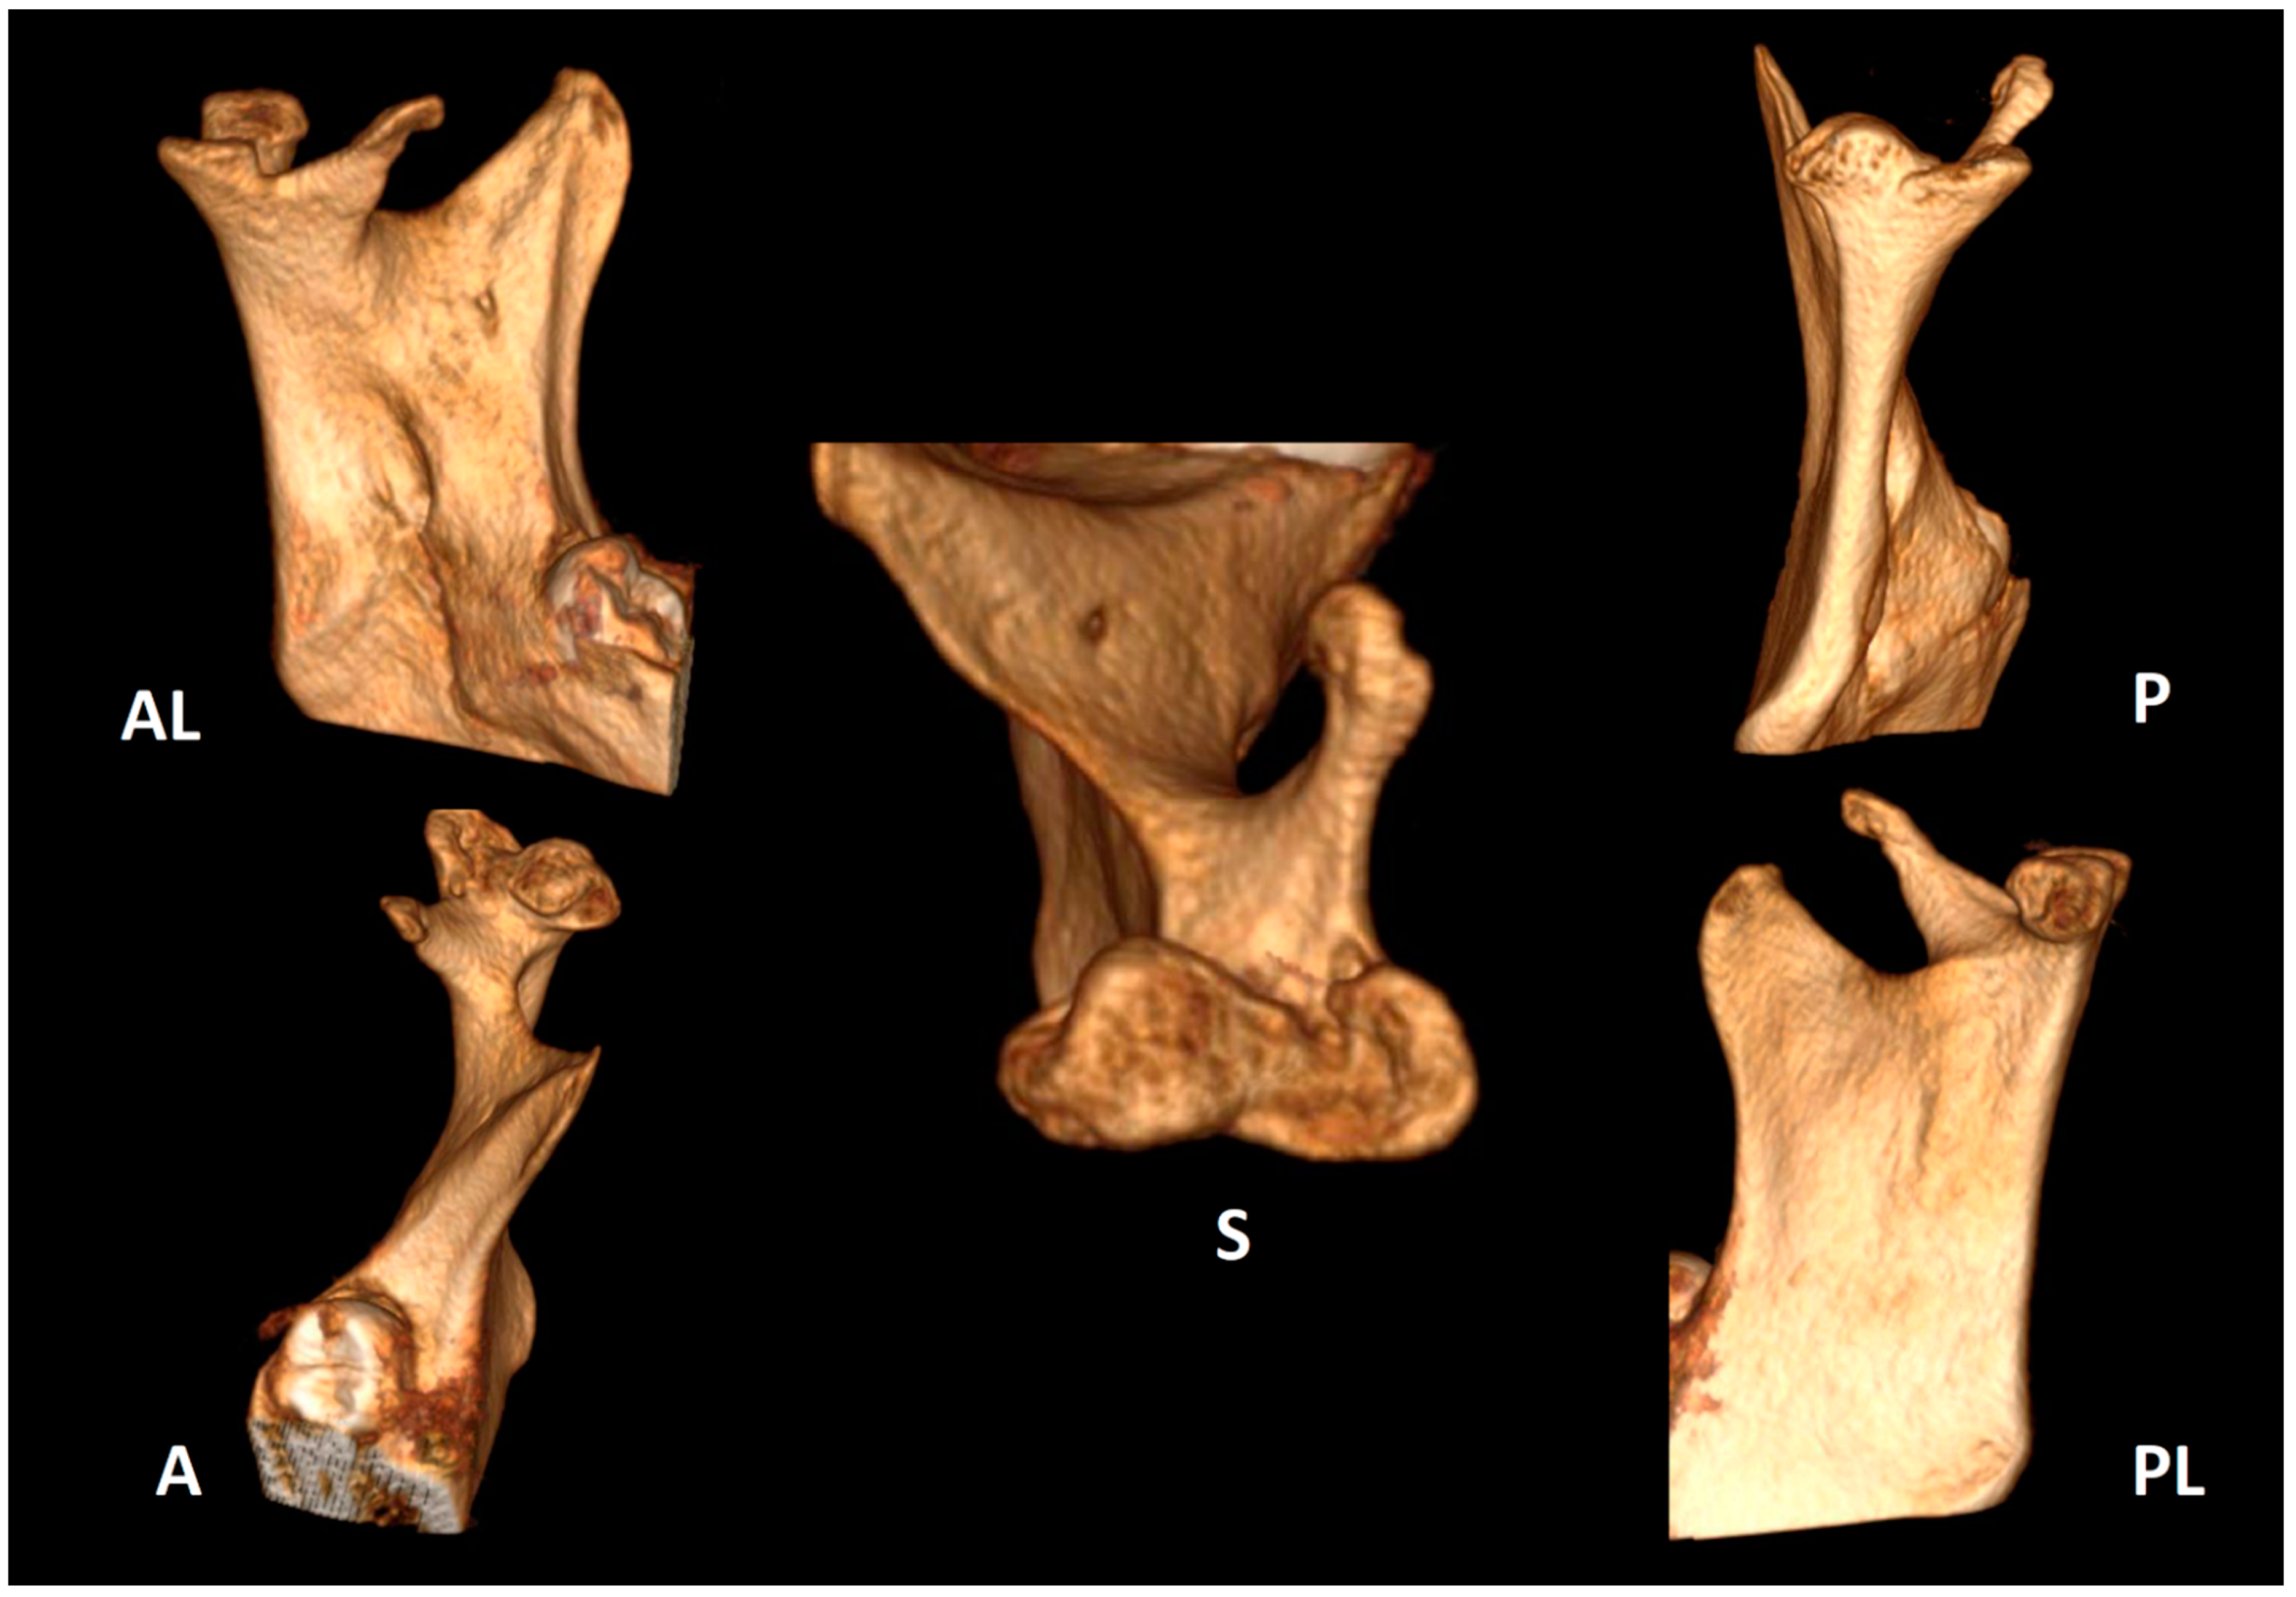

Trifid Mandibular Condyle: Case Report and Current Review of the Literature

2. Case Report